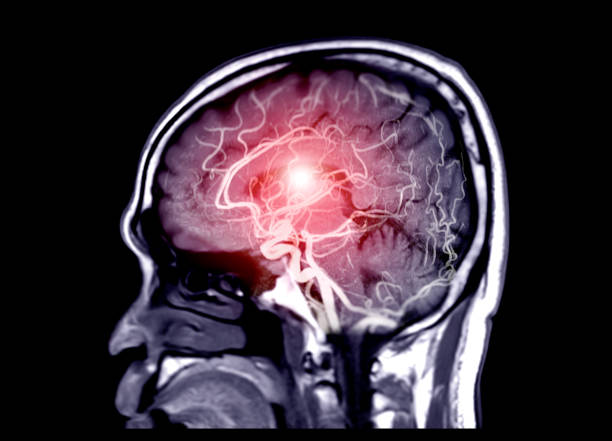

고혈압은 뇌출혈의 가장 큰 원인으로 볼 수 있는데 고혈압 환자라면 혈압이 갑작스럽게 상승하는데 이 때 산소와 영양소가 뇌로 들어가는 통로인 혈관에 변화를 일으키는데 혈관이 버티지 못하고 터지게 됩니다. 뇌동정맥의 기형에 의한 뇌출혈, 뇌동맥류 파열에 의하여 나타나며 잦은 흡연이나 다른 질병의 합병증으로 인해 발생할 수 있으며 뇌손상은 팔, 다리, 심하면 얼굴등 신체 일부분이 평생 마비시키며, 골든타임을 놓칠 경우 사망할 수도 있어 뇌출혈 전조증상에 대해 알고 있는 것이 좋습니다.

뇌출혈 전조증상 첫 번째는 두통입니다. 두통은 누구나 겪는 흔한 현상이기 때문에 무시당하는 상황이 많은데 이 때문에 골든타임을 그냥 지나게 됩니다. 하지만 뇌출혈로 인한 두통은 정상적인 두통보다 더 심하게 나타나는데 이 두통의 요인이 뇌동맥류에서 기인하기 때문이기 때문에 평소와 다른 두통이라면 뇌출혈을 의심해봐야 합니다.

뇌출혈 전조증상 두 번째는 마비 증상과 동반한 구토 및 메스꺼움입니다. 뇌 출혈이 우뇌에서 생기는 경우 왼쪽에서 마비가 좌뇌에서 생기는 경우 우측에서 마비가 생길 수 있으며 이와 동반하여 어지러움, 메스꺼움, 구토 등의 증상이 나타날 수 있는데 이러한 증상은 혈압 상승으로 인해 기온이 떨어지는 겨울철에 발생하기 쉽습니다.

뇌출혈 전조증상 세 번째는 시력과 균형감각의 상실을 이야기 할 수 있습니다. 뇌 혈관 문제로 생기는 뇌출혈은 시신경과 관련하여 시야가 흐려지고 눈을 정상적으로 뜨기 어렵기 때문에 시력을 이부 상실할 수 있으며 균형 감각도 둔해져 가만히 있더라도 몸이 계속 기울어져 넘어질 수 있습니다.